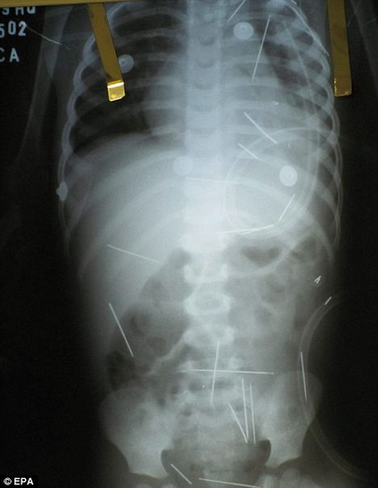

孩子體內的一根根縫衣針令人觸目驚心

主治醫生路易斯表示,通過X光片看到孩子體內竟然有50根縫衣針,他們真是大吃一驚,有好幾根針甚至長達5厘米,但是孩子身體表面卻看不出任何傷口。路易斯說:“這些針肯定是被人一根一根扎進體內的。我們在孩子的肺、左腿和胸腔都發現很多針,根本就不可能是孩子自己吃下去的。”

據醫生介紹,借助手術他們可以取出一些針,但是有幾根恐怕只能一直呆在男孩體內了,因為它們離孩子的重要器官太近,取針反而十分危險;而扎在孩子肺部的那幾根針,也得等到孩子的呼吸穩定了之后才能動手術取出。